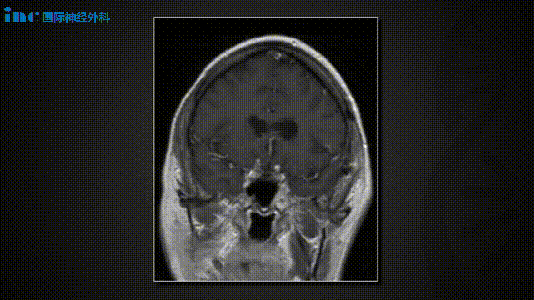

术后恢复过程平稳。患者于术后第5天出院,期间仅出现一过性外展神经麻痹,该症状在术后6周内完全恢复。术后听力检测证实听力功能得以保留。术后4个月随访MRI显示两处肿瘤完全切除,无残留复发征象。

(术后MRI)

术后影像与临床病程

术后影像证实两处病变均获全切。患者术后出现一过性左侧外展神经麻痹,6周后完全恢复,听力保存完好。